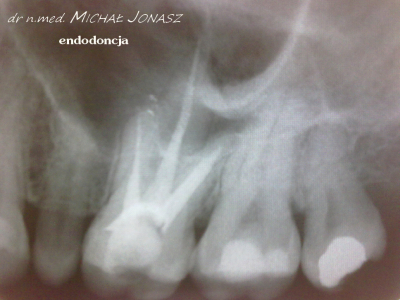

Zmiany okołowierzchołkowe to ogniska zniszczenia kości wokół wierzchołków korzeni zębów. Przewlekłe, nieleczone zmiany zapalne w obrębie korzeni zęba mogą powodować duże uszkodzenia kości i skutkować utratą zębów. Reendo polega na usunięciu materiału, którym wypełnione są kanały i zlokalizowaniu nieprawidłowości, czyli niedostatecznie oczyszczonego lub wypełnionego kanału albo pozostawionego, złamanego narzędzia w jego świetle. Dzięki mikroskopowi problemy anatomiczne, takie jak wąskie, zarośnięte kanały, zakrzywione korzenie, boczne, nietypowe odnogi są możliwe do wyeliminowania.

Diagnostyka obrazowa i wprawne oko Stomatologa są podstawą do podjęcia powtórnego leczenia kanałowego. Wychwycenie zmian patologicznych kierujących na powtórne leczenie kanałowe często jest efektem wnikliwej analizy zdjęć RTG. Powtórnego leczenia kanałowego wymagają zęby, których kanały korzeniowe nie zostały prawidłowo wypełnione. Im dłuższy czas upływa od zakończenia pierwotnego leczenia kanałowego, tym mniejsza szansa, że ząb da o sobie ponownie znać. Nieprawidłowo przeleczony kanałowo ząb, to potencjalnie ogromne ryzyko dla pacjenta. Ząb źle leczony kanałowo przypomina o sobie po wielu latach, bądź w postaci dolegliwości bólowych, bądź przez wolno, bezobjawowo rozwijającą się torbiel. Wytworzenie się torbieli wymaga już interwencji z zakresu chirurgii stomatologicznej. W takiej sytuacji po leczeniu powtórnym pacjent jest kierowany do chirurga na zabieg wyłuszczenia torbieli.

Na zdjęciu RTG efekt leczenia endodontycznego można ocenić po 3 – 6 miesiącach. Każde kanałowe leczenie należy systematycznie kontrolować poprzez wykonywanie rutynowych zdjęć radiologicznych, tak by zawczasu uniknąć nieprzyjemnych problemów.